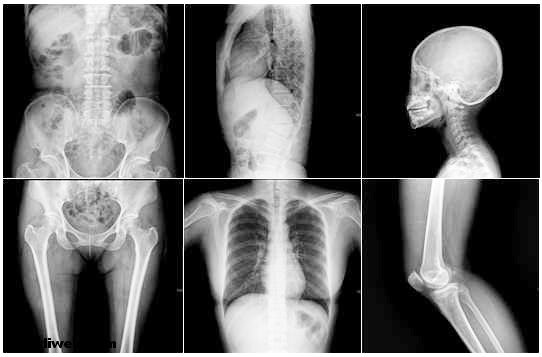

Wilhelm Conrad Röntgen 1845 yılında Rheinland’da doğdu ve 1923 yılında Münih’de öldü. Münih Üniversitesi Fizik Kürsüsü ve Yeni Fizik Enstitüsü yöneticisi olan Wilhelm Conrad 1895 yılında X ışınlarını keşfetti.  Her geçen gün tıp alanında gelişmeler artıyor. Bu gelişmelerin temelinde tarihte daha kısıtlı şartlarda büyük buluşlar yapan bilim adamlarının yeri yadsınamaz. Hatta binlerce senelik uzun dönem içerisinde pek çok şey gibi tıpta kullanılan aletler de vardır. İlkel kültürlerde tendondan iplikler ve kemikten iğneler kullanılmasından, çakmak taşından yapılmış bıçak biçimindeki cerrahi aletler ile kafatasında delik açma gibi insanoğlu tıp alanında birçok çalışma yapmıştır. 17. Yüzyılda Aydınlanma Çağı ile birlikte tıp alanında önemli gelişmeler başlamıştır. Bu gelişmeler ile cerrahi uygulamaların ilerlemesi medikal alet ve cihazlarının sanayileşmesine ve bu sanayiye yönelik teknolojinin de ilerlemesine yol açmıştır. Tıbbi cihazların en fazla gelişen alanlarından biri olan tıbbi görüntüleme teknolojisi 1895’de Wilhelm Conrad Röntgen ’in ilk X-ışın tüpünü bulması ile başladı. Bu buluş aynı zamanda tıp alanında yeni bir dönemin başlangıcı olmuş, başlangıçta kemik kırıklarının tanısında bu ışınlar yoğun olarak kullanılmıştır.

Zürih’te üniversite öğretimi gören, Strassburg, Giessen ve Würzburg’da fizik profersörlüğü yapan Wilhelm Conrad Röntgen 1885 yılında kutuplanmış bir yalıtkan hareketinin, bir akımla aynı manyetik etkileri gösterdiğini açıkladı. Fakat asıl ününü, 1895 yılında X ışınlarını keşfetmesiyle kazandı. Bu ışınları inceleyen Röntgen, X ışınlarının bir doğru boyunca yatıldığını, yansıma ve kırılmaya uğramadığını, elektrik veya manyetik alanların etkisiyle yön değiştirmediğini ispatladı. X ışınlarının, cisimlerin içinden geçme kabiliyetlerini inceledi ve bu ışınların havayı iyonlaştırdığını ortaya çıkardı. 1901 yılında tamamladığı bu araştırmaları sonucu, aynı yılın fizik dalında Nobel Bilim Ödülü’ne layık görüldü. X veya g ışımalarının miktar ölçümü birimine kendi ismini vermiştir. Günümüzde röntgen ışınları tıp alanında kullanılmaktadır.